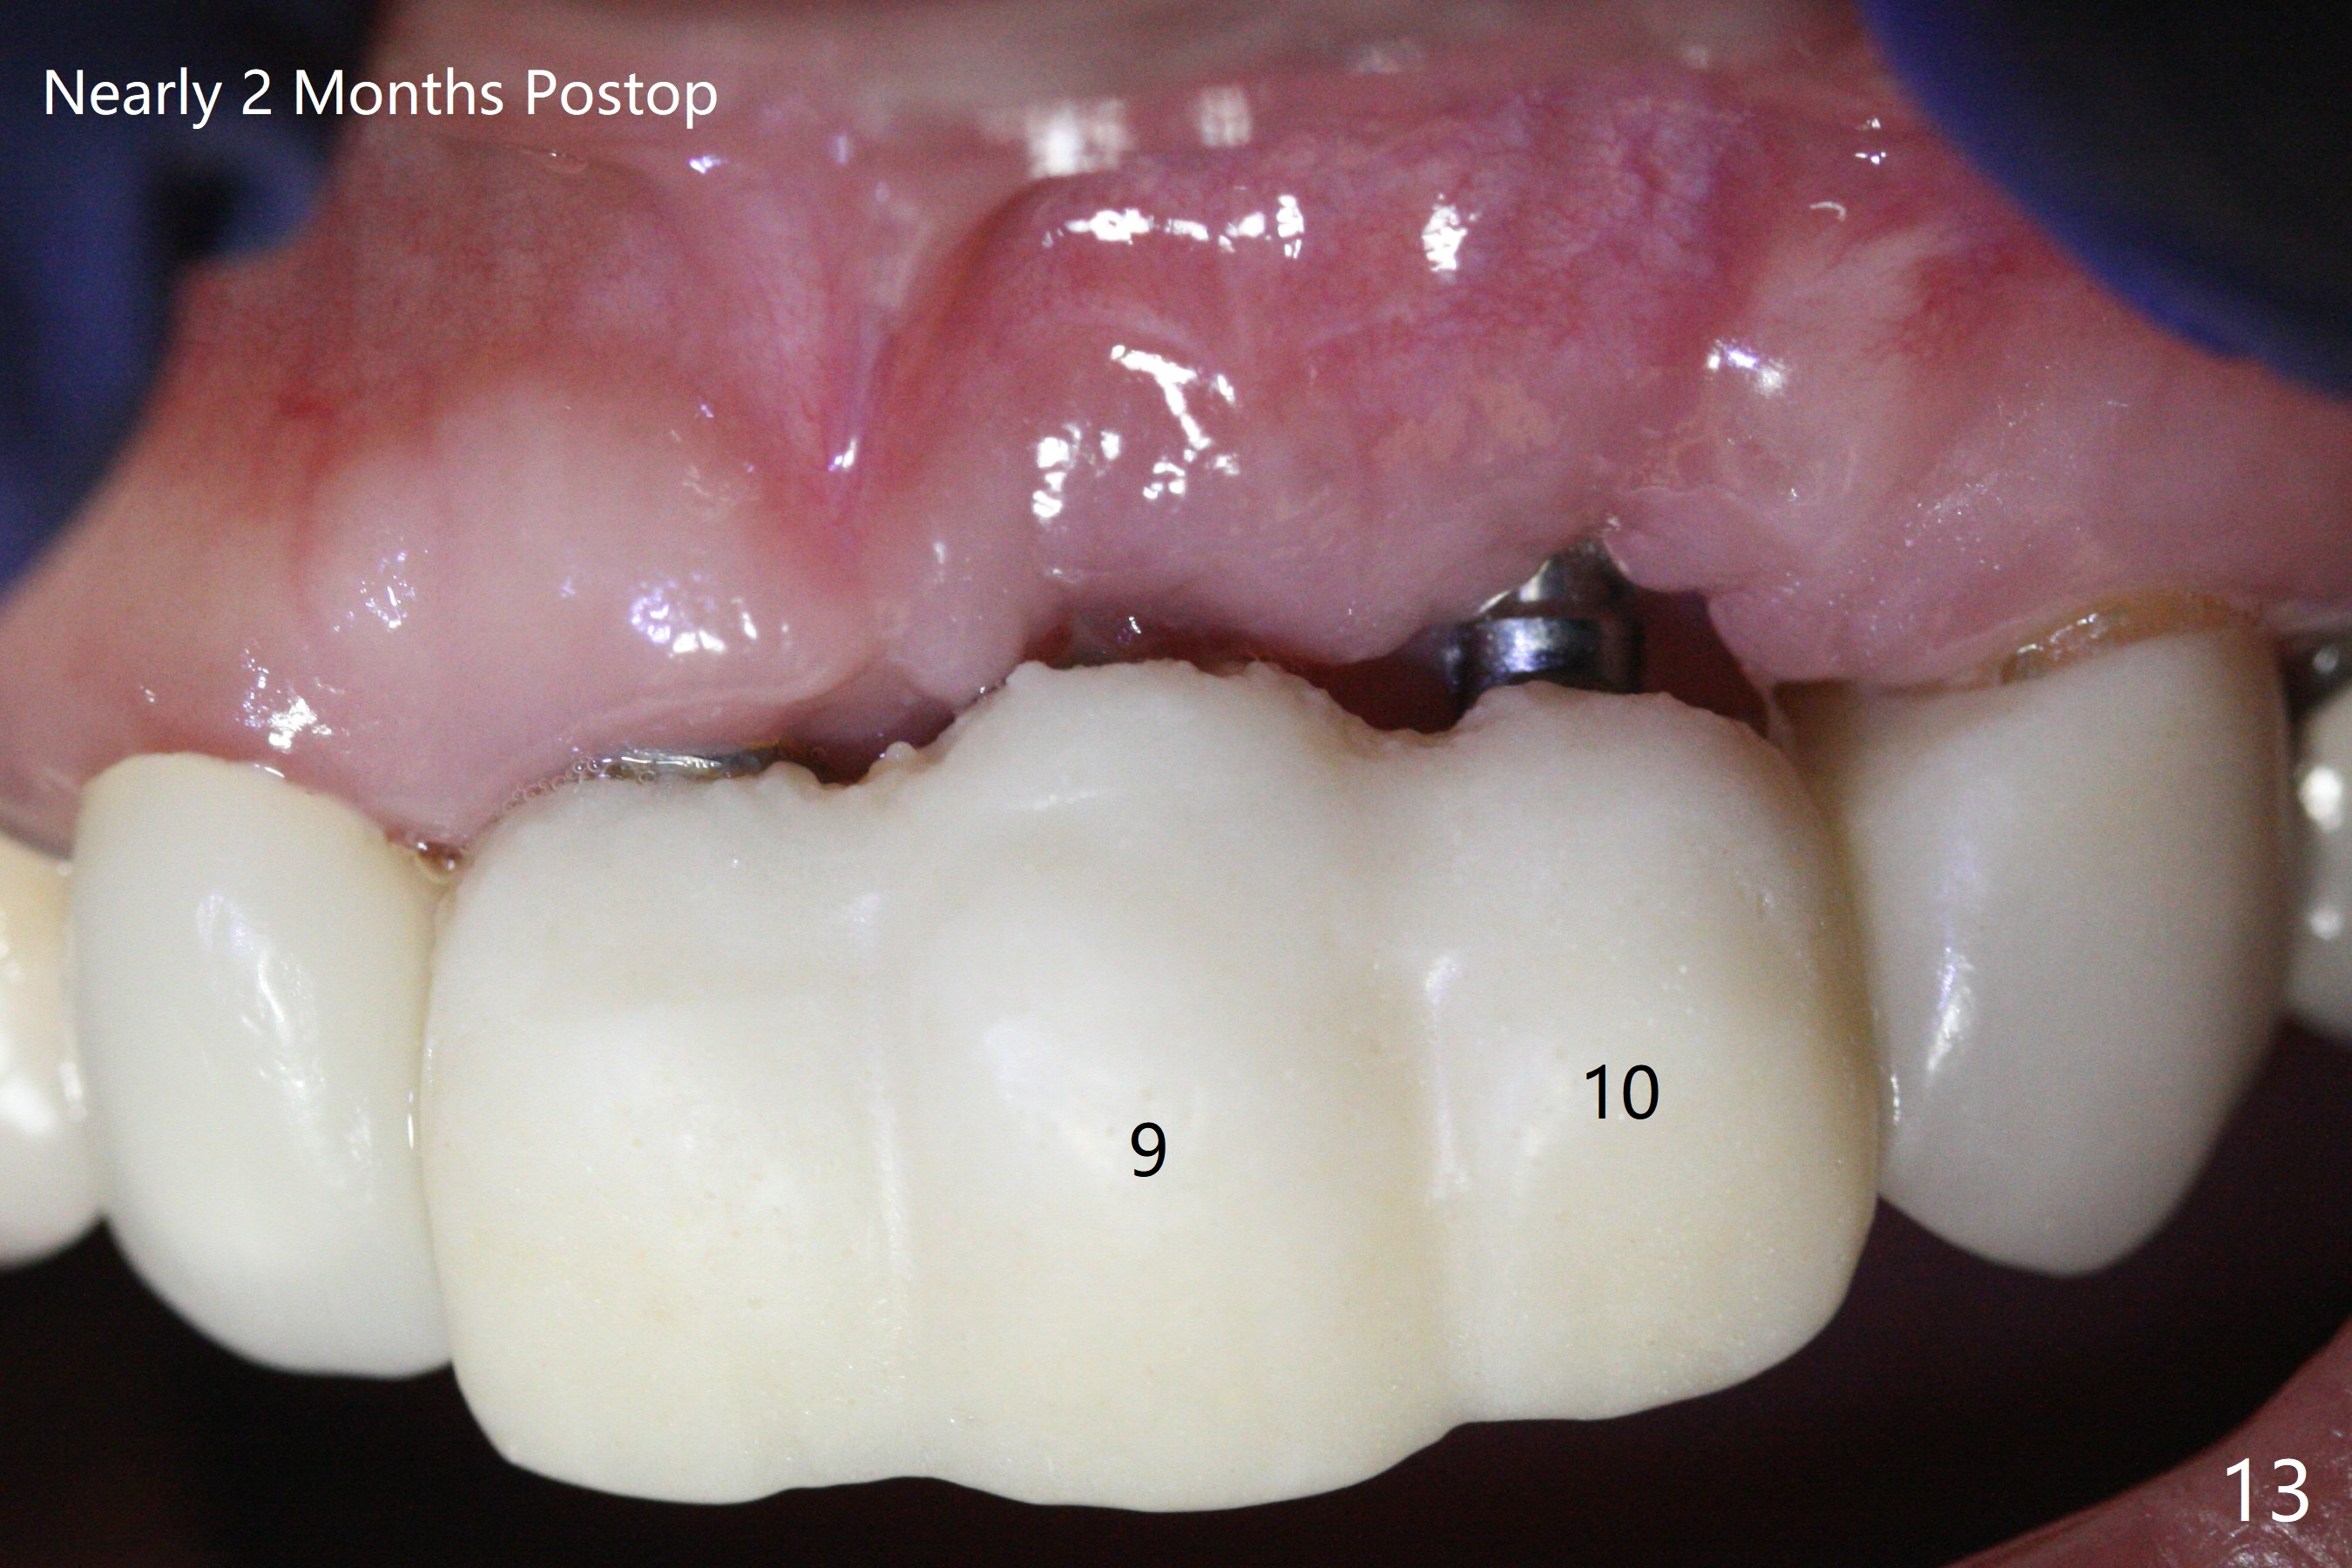

Incision shows exposure of microthreads at #9 and major threads at #10 due to buccal placement (Fig.1). There is bone palatal to the implant at #10 (Fig.2 P), to which a new implant will move. After implant removal, a narrower 1-piece implant (2.5x14(4) mm) is placed palatally at #10 (Fig.3,4) in combination of guide and free hand. At the site of #9 after implant removal, the guide is not used; a 3x17 mm angled 1-piece implant is placed with bad trajectory (Fig.5,6). After re-adjustment (Fig.7), the implant is placed at the right orientation (Fig.8). It appears that the guide is helpful. Allograft is placed mainly buccally (Fig.9,10 *), followed by a piece of collagen membrane (Fig.11). After tension release, flaps are approximated (Fig.12). The buccal gingiva at #9 and 10 recede nearly 2 months postop (Fig.13). Less recession at #9 is associated with more inflammation (Fig.14). The margin of the provisional is adjusted for gingival margin down growth and easy self cleaning with Water Pik (Fig.15). One month later, the gingival inflammation reduces, while there is no obvious buccal collapse (Fig.16,17). Impression is taken after laser gingivectomy nearly 4 months postop (Fig.18). While the gingiva around the implant at #9 is inflamed (periimplantitis?), the gingival cuff at #10 is well formed 5.5 months postop immediately before cementation (Fig.19). The buccal concavity at #10 is minimal (Fig.20). The gingival inflammation at #9 will be hopefully resolved after cementation of the final restorations (Fig.21). There appears to be new bone formation around the coronal implant threads 5.5 months postop (immediately post cementation, Fig.22). The microthreads at #9 may be not covered by the bone, the reason for the gingival erythema. The redness at #10 is asymptomatic 5.5 months post cementation (Fig.23). 粘固后两年牙槽嵴骨质并没有再生(图二十四),说明第一术中植体必须植入骨下(基台部分要长,否则难于修复),第二牙槽嵴处不应该有压力,植入2.5毫米植体,最后钻头应该是2.5毫米,骨下1-3毫米(尝试项目)。